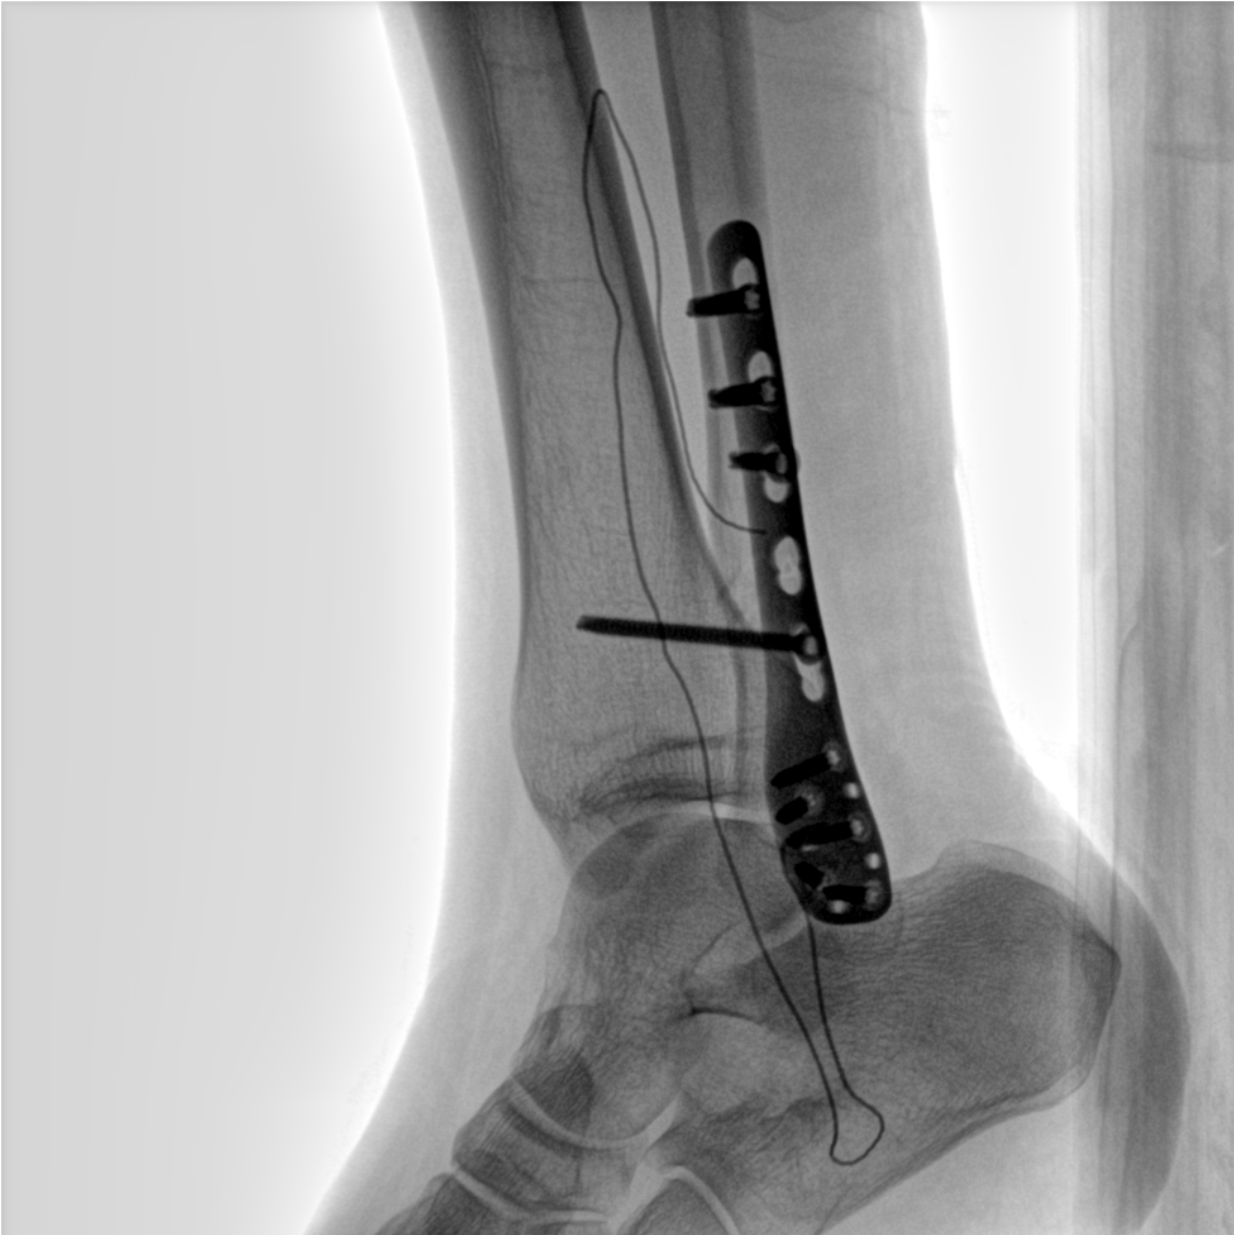

術(shù)中三維成像和橫斷面圖像提供多角度的手術(shù)診斷信息,輔助醫(yī)生進(jìn)行術(shù)中評估判斷,諸如骨折復(fù)位情況和內(nèi)植入螺釘?shù)某叽绾臀恢?,輔助手術(shù)更好地完成。